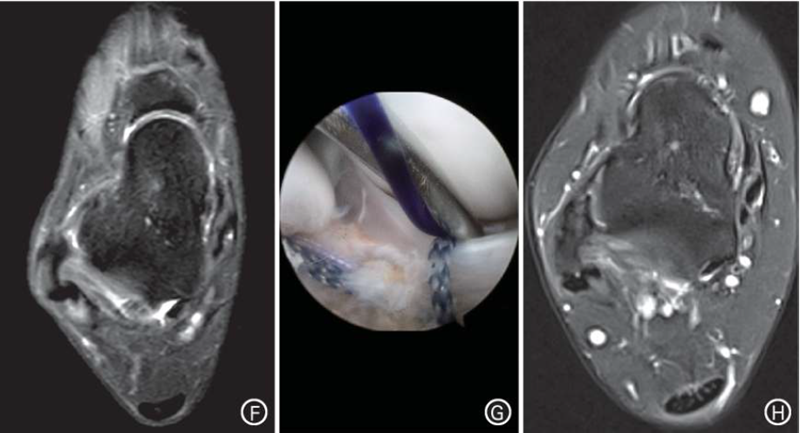

典型病例,患者男,19岁,右踝习惯性扭伤后疼痛不适1年余。入院诊断:(1)右踝关节ATFL损伤,慢性踝关节不稳;(2)全身多韧带松弛症(Beighton评分5分)。入院3d后行关节镜下改良Broström法ATFL修复术。

图1 A~E.患者体检显示Beighton评分为5分;F.术前MRI示右踝关节ATFL慢性损伤;G.术中将撕裂的ATFL残端通过锚钉缝线收拢至腓骨远端,然后打结拉紧;H.术后24个月MRI示右踝ATFL连续,未见明显松弛。注:ATFL为距腓前韧带